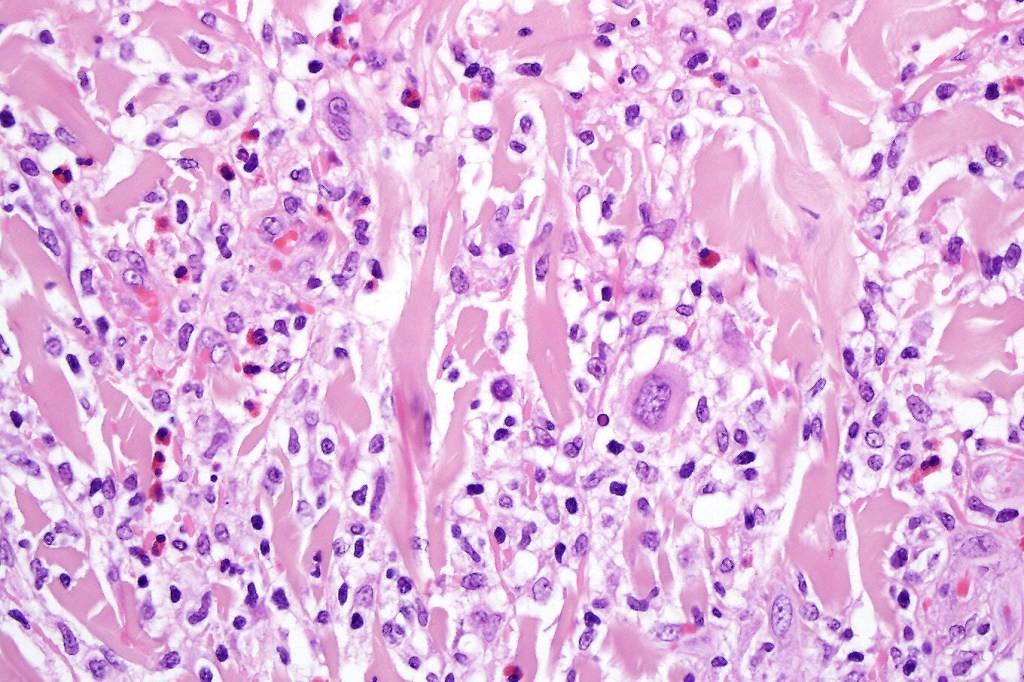

•Type B: 5-10% resembles plaque stage mycosis fungoides

Type B variant is histologically indistinguishable from mycosis fungoides. Type D variant is indistinguishable from other epidermotropic lymphomas.